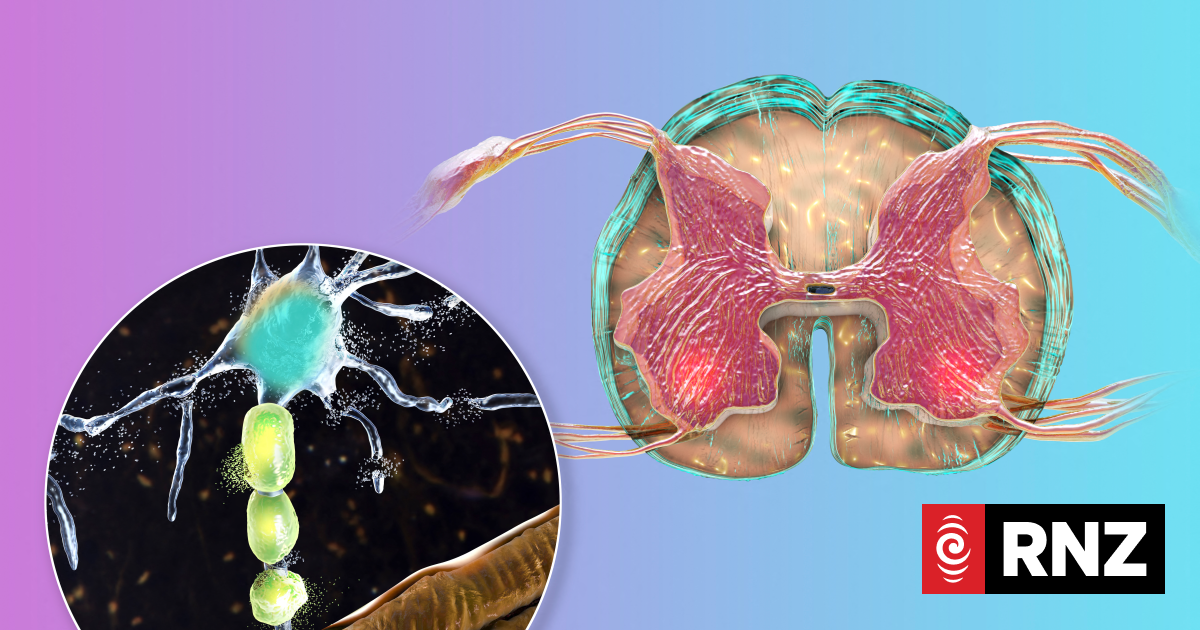

Illustration of motor neuron diseases, showing degeneration of motor neurons in anterior horns of spinal cord.

Photo: Science Photo Libra via AFP